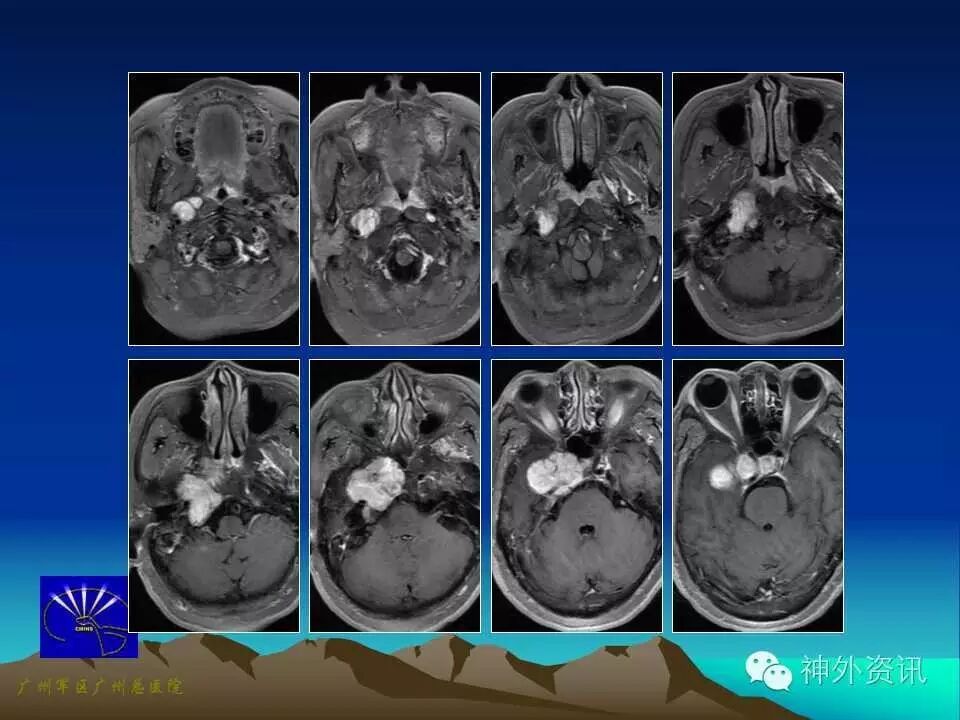

肿瘤经正常的腔隙、孔道或破坏颅底骨质侵犯颅内外相关结构,称之为颅底沟通瘤。由于此类肿瘤位置深在,毗邻解剖结构复杂,可涉及多个学科,肿瘤难以全切,颅底缺损重建较为困难,肿瘤残留率和复发率较高,且术后易出现新的神经功能障碍,如何提高手术治疗效果仍是目前颅底外科相关专业研究探索的难题之一。

选择合适的手术入路以达到最佳的暴露视角、最短的手术距离和最小的脑牵拉一直是颅底外科的核心。到目前为止,颅底沟通瘤手术入路的选择尚无统一标准,不同作者从各自专科角度和手术特点出发,对手术入路的选择存在一定差异。由于颅底沟通瘤病理类型多样,生长部位、范围和方向不尽相同,因此,术前应根据肿瘤的三维结构个性化选择最佳手术入路。

颅中窝沟通瘤通常向下突破进入颞下窝或翼腭窝,或由颞下窝肿瘤进入颅中窝。可采用额颞颧入路,具体手术方式为:仰卧位,头抬高15度,向健侧旋转45度,切口始于颧弓根下方1.0cm,过颧弓后弯,向前至中线止于发际内。切开皮肤后筋膜间分离额颞部皮瓣,骨膜下显露眶缘与颧弓,离断颧弓后将颞肌翻向颧弓下方。该法也称改良扩大翼点入路,在硬脑膜外能较好显露颅中窝底及其邻近结构。也可采用经额颞联合耳前颞下入路,方法同上,但切口向下越过颧弓延至下颌角处,颧面部沿腮腺筋膜浅层翻起,分离平面在颞筋膜外层,避免损伤面神经额颞支。颧弓下方由颞窝内游离颞肌,将肌瓣与已断离的颧弓一起翻向下外侧。磨除蝶骨嵴及部分蝶骨大翼,使术野开阔,更有利于切除鞍旁、颅中窝底及颞下窝肿瘤向颅外生长的部分。对肿瘤向侧方生长累及鞍旁、海绵窦、颅中窝底和颞下窝单侧沟通瘤,该入路由于去除了眶缘和颧弓的阻挡,颅底显露角度明显扩大,可将眶顶、眶侧壁及蝶骨二翼直接暴露,磨除蝶骨嵴,稍牵开硬脑膜,满意显露眶上裂与颞下窝等部。手术多在硬脑膜外做,对脑组织牵拉伤小,显微镜下分块切除瘤组织,避免了误伤重要血管神经。对血供丰富的肿瘤,可术前行血管内栓塞或颈外动脉结扎,有利肿瘤全切。对颅内外肿瘤切除后留下的死腔,可用附近颞肌瓣等填充以消灭死腔。颅底重建包括硬脑膜与颅底骨缺损的重建。一般而言,对颅底骨质缺损<4.0cm×3.0cm者,可仅采用帽状腱膜骨膜瓣修补,术后无脑膜脑膨出等并发症发生;若颅底骨质缺损>4.0cm×3.0cm者,可采用额部帽状腱膜骨膜瓣-钛网-颞肌筋膜瓣的三明治法修补重建。颅底沟通瘤术中可能需要填充大量止血材料,术后应在1周内复查MRI,术后3个月再次复查MRI,重点对比观察T1增强图像,以判断肿瘤切除程度。肿瘤全切者无需后续治疗。对侵犯海绵窦、包绕颈内动脉或侵犯视神经、三叉神经、面听神经等重要神经的肿瘤,通常难以全切除,术后可辅助立体定向放射外科治疗。